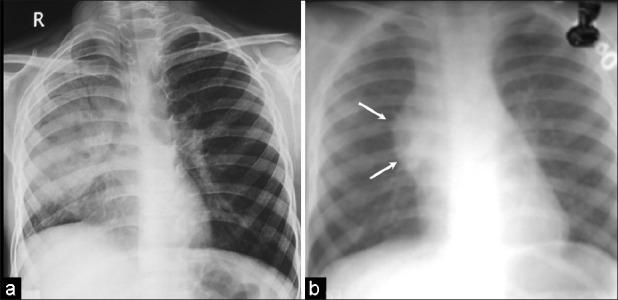

Benign mediastinal teratomas are commonly asymptomatic and seldom cause complications. Spontaneous rupture into the pleura is rare and cross-sectional imaging is crucial in its early detection and planning a proper surgical approach. We report two cases of spontaneous pulmonary and pleural rupture of benign mediastinal teratoma and discuss the imaging appearances.

良性纵隔畸胎瘤通常无症状,很少引起并发症。自发破裂入胸膜罕见,横断面成像对其早期检测和规划合适的手术方法至关重要。我们报告两例良性纵隔畸胎瘤自发破裂至肺和胸膜的病例,并讨论其影像学表现。